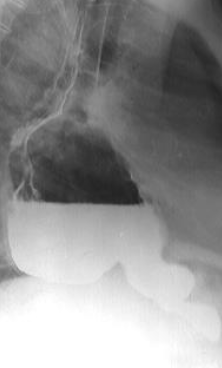

Ulcer piloric

Steoză pilorică

Stenoză mediogastrică